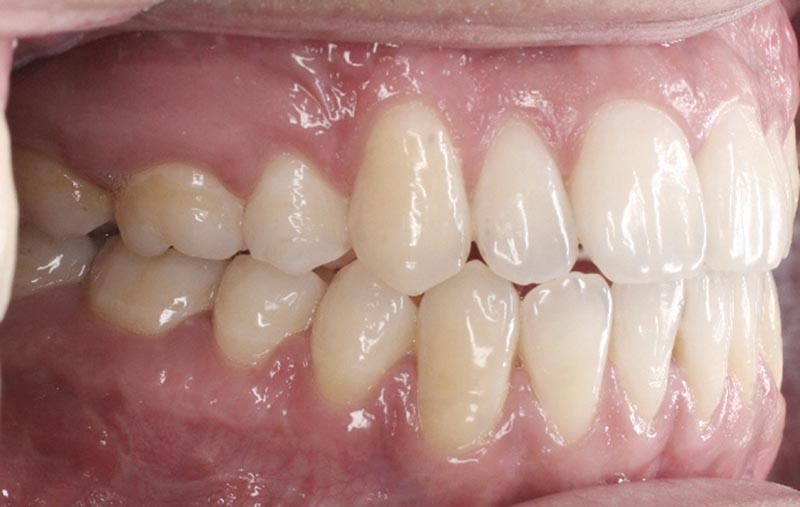

Les résultats esthétiques et occlusaux satisfont amplement le patient qui revient pour un contrôle à long terme 10 ans après l’intervention montrant la stabilité des résultats.